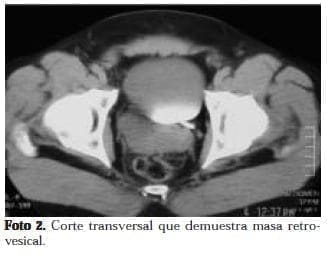

Varón de 37 años, quien consultó al servicio de urgencias por orquialgia derecha. Al examen físico se anotaba masa palpable a nivel del polo superior del testículo derecho dolorosa, mal definida. Con sospecha de neoplasia testicular, se solicitaron estudios de extensión y se llevó el paciente a orquidectomía radical derecha. El reporte de patología fue de isquemia testicular. Sin embargo, en la tomografía se reporta la presencia de una masa retrovesical y agenesia renal derecha. Como hallazgo incidental (Fotos 1 y 2). Los radiólogos recomiendan realizar resonancia magnética nuclear para aclarar el diagnóstico.

La resonancia muestra una masa multiloculada (foto 3 y 4) dependiente de la vesícula seminal derecha y agenesia renal ipsilateral. Se realizó además una ecografía transrectal de próstata, donde se identificó una gran masa quística que rechaza la pared posterior de la vejiga.